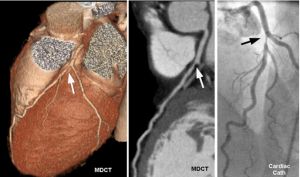

心電圖運動試驗陽性但無症狀;冠狀動脈造影有明顯的血管狹窄而無症狀;未被識別或無症狀的心肌梗死;既往無症狀而發現陳舊心肌梗死;慢性穩定性心絞痛病人,一日之內頻繁而短暫的發作ST段壓低,壓低次數的70%~85%無症狀,僅24%伴有胸痛;無先兆症狀的猝死。所以我們必須掌握有關的知識,提高警惕,及時就診,防止延誤病情而導致嚴重的後果。

無症狀型冠心病的診斷培養免疫主要根據靜息動態或無症狀冠心病負荷試驗的心電圖檢查和(或)放射性核素心肌顯像發現每天患者有心肌缺血的改變而無其他原因又有動脈粥樣硬化的危險因素移植進行選擇性冠狀動脈造影檢查可確立優秀診斷。

診斷和鑑別診斷:診斷主要根據靜息、動態或負荷試驗的心電圖檢查,和(或)放射性核素心肌顯像,發現患者有心肌缺血的改變,而無其他原因,又有動脈粥樣硬化的危險因素。進行選擇性冠狀動脈造影檢查可確立診斷。